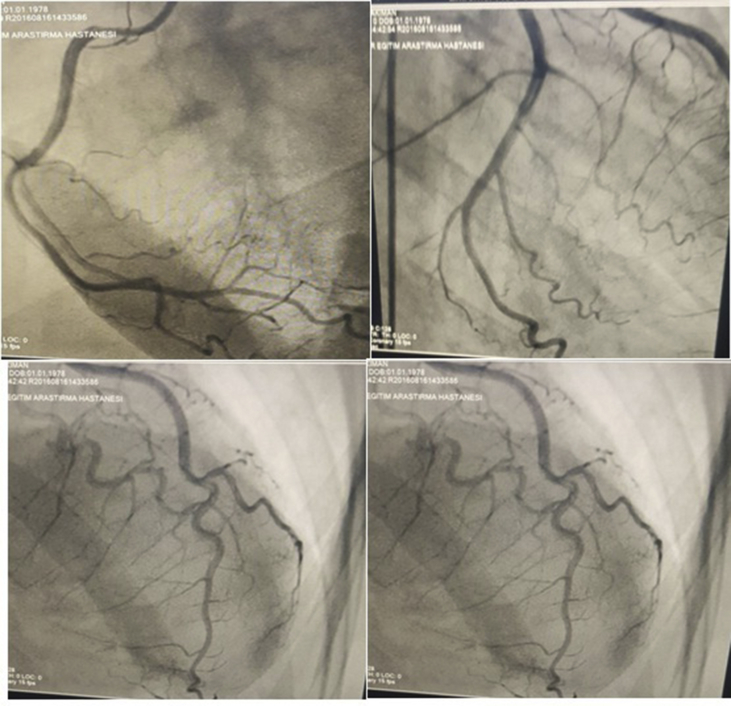

A 23-year-old male patient was admitted to our emergency department with a severe chest pain accompanied by a shortness of breath that started 2 h previously. According to the patient, his pain has the characteristic of spreading to the jaw, the left arm, and the back region. An electrocardiography (ECG) was performed the ninth minute from when the patient entered the emergency room. On the II, III, and VF derivations of the patient's ECG, a 6-mm ST-segment elevation was observed (Fig. 1). On the echocardiography taken in the emergency department, there was a hypokinesia in the inferior part of the myocardium. The patient had no cardiac risk factors for coronary artery disease, no history of recent emotional or physical stress. The cardiac risk factor for coronary artery disease was not pre-existing for the patient, and there was no other health problem, as well. In the meantime, the patient also had no emotional or physical stress exposure. The patient stated that about 4–5 hours previously, he had swallowed 2–3 Captagon tablets with a glass of water containing a phenylethyl-active agent in a recreational environment, in order to feel excitement and pleasure. A physical examination revealed the patient's state of consciousness, and the Glasgow Coma Scale as 15. The general condition of the patient was good, and the vital findings were stable; however, a slight agitation and restlessness were present. The blood pressure was 135/95 mmHg, the number of beats per minutes (pulse) was 115, the respiratory rate was 26 breaths per minute, and the oxygen saturation was 96%. An urgent diagnostic coronary angiogram within 2 hours of the onset of chest pain revealed normal right and left coronary artery systems. (Fig. 2). In the laboratory, the results of the first hour were as follows; troponin I value, 3.4 (normal <0.01 ng/ml); CK-MB value, 27.6ng/ml (N: 0–8.59), and the other laboratory tests were normal and there was no abnormality on the chest x-ray. The patient was hospitalized in the intensive care unit and the chest pain was improved and the elevation of ST in ECG returned to normal in the sixth hours after initiation. Because the coronary arteries were normal, the patient was discharged after adding Diltiazem 60 mg orally three times a day to the treatment. After fifteen days, the hypokinesia in the echocardiography of the patient without any angina pectoris had disappeared.

Fig. 2.

Normal angiographic appearance.

Although the pathophysiological mechanism is not fully explained, one of the serious side effects of coronary artery narrowing due to amphetamine use has been reported to be an acute myocardial infarction (AMI).9 In the literature, a case with AMI due to the use of HCl, which has been suggested to have an amphetamine-like effect, has been reported.3 Phenylethyline, along with a coronary vasospasm, causes small and medium doses to expand to the bronchial vessels and increase the heart rate, body temperature, respiration, and blood pressure.1 In our case, the second known case, there was acute inferior MI, tachycardia, and a blood pressure increase due to a vasospasm. PEA HCL is illegally present in European countries and in particular, it is produced in Turkey and is one of the most common substances used by the young and wealthy people in the Middle East. PEA is the name of a trademark containing the causative agent 'phenethylamine hydrochloride: a synthetic stimulant that is a central nervous system stimulant with euphoric and analgesic properties. The intake of this medicine can be by swallowing and application to the skin, vagina, and peritoneus. It has been reported that students and military students preparing for examinations use these oral tablets as an anorectic agent to keep awake or to lose weight.1 When the literature is examined, it seems that there are no enough resources related to the toxic clinical features that originated in Captagon. Among the side effects of the drug insomnia, restlessness, irritability, nervousness, excessive euphoria, and over-excitement of the central nervous system can be listed. Several case reports are available in the literature with paranoid delusions and disorientation due to PEA use with the symptoms disappearing quickly after stopping the drug.10 Although there is no enough evidence, cardiac insufficiency and cardiomyopathy are associated with the use of Captagon tablets in younger individuals. A case with visual problems due to retinal vein occlusion caused by the PEA drug use has already been reported.11 In another report in Turkey, due to the abuse of Captagon tablets, AMI has been reported. It has been reported that a young male patient was admitted to the emergency service with chest pain, tachycardia, palpitations, and aggressive behavior after taking Captagon pills. A coronary vasospasm was detected on the angiography of this patient with ventricular fibrillation.3 Although there was evidence of ECG inferior AMI in young male patients who reported that they were taking Captagon tablets, their angiography was normal. It is estimated that in our case in which the angiography was evaluated, an acute inferior myocardial infarction resulted from a vasospasm associated with the use of Captagon tablets. Nevertheless, there is a need for more extensive and advanced studies to prove this hypothesis.